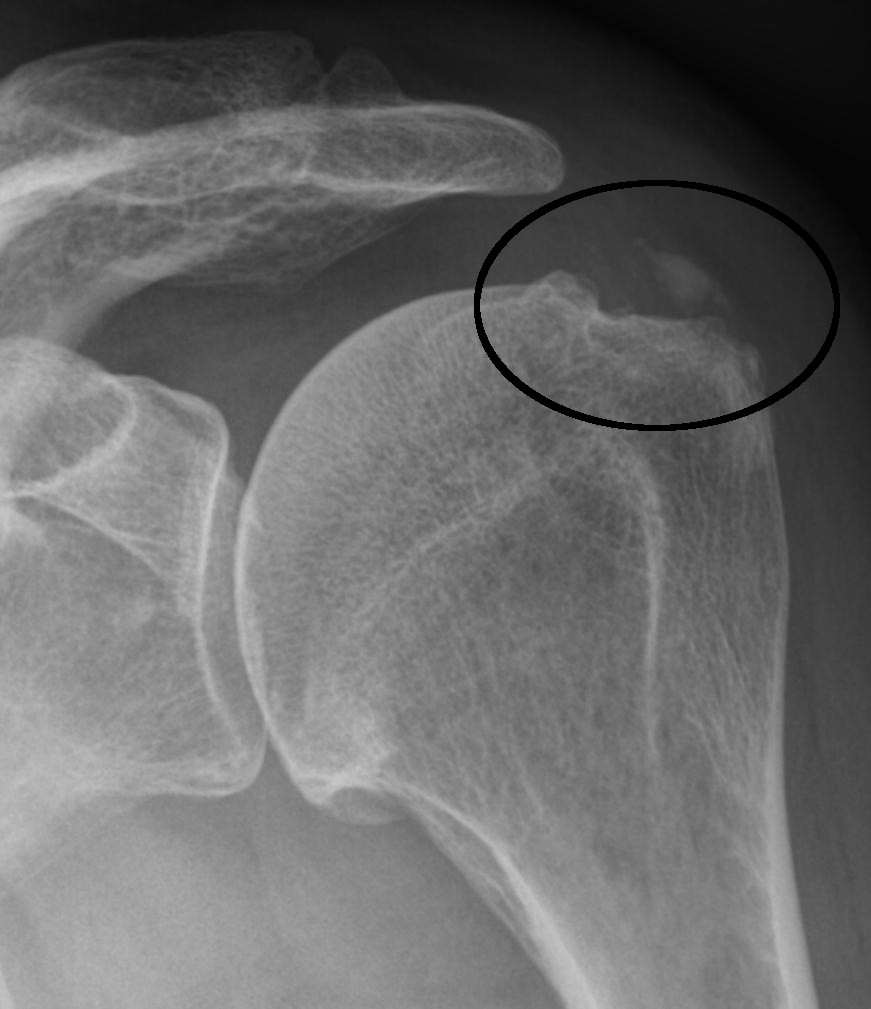

Die Kalkschulter, auch Tendinosis calcarea genannt, ist eine schmerzhafte Erkrankung der Schulter. Sie entsteht durch Kalkablagerungen in den Sehnen der Rotatorenmanschette, einer Muskelgruppe, die für die Beweglichkeit der Schulter verantwortlich ist.

Diagnose: Wie wird die Kalkschulter Diagnostiziert?

Die Diagnostik der Kalkschulter in unserer orthopädischen Privatpraxis zeichnet sich durch besondere Sorgfalt aus. Wir wissen, dass Kalk in der Schulter nicht immer Schmerzen verursacht und umgekehrt. Deshalb ist unser erster Schritt eine umfassende Anamnese und eine gründliche Untersuchung. Dieses Vorgehen ermöglicht es uns, die wahren Ursachen Ihrer Beschwerden zu identifizieren und sicherzustellen, dass unsere Diagnose präzise ist.

Modernste Ultraschallgeräte erlauben uns die detaillierte Betrachtung der Weichteile Ihrer Schulter sowie der Sehnen der Rotatorenmanschette. In bestimmten Fällen ergänzen wir diese Untersuchungen durch ein MRT, dieses kann zwar den Kalk nicht darstellen, kann jedoch eine Sehnenentzündung, Teilrupturen oder eine Schleimbeutelentzündung noch detaillierter darstellen als der Ultraschall.